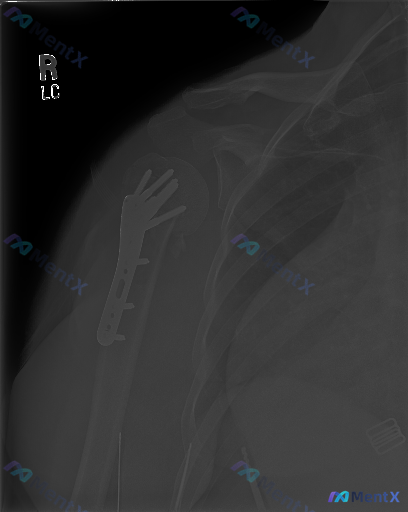

整理到一张右肩部及上臂正位X光片的资料,来自一位肱骨近端骨折术后复查的患者。 影像上能看到:右肱骨近端外侧有金属接骨板和数枚螺钉固定,螺钉位置在骨骼内,未见明显金属断裂或松动;骨折断端(推测外科颈附近)有连续骨痂形成,骨小梁有跨越迹象,皮质连续性良好,未见新发骨折线;盂肱关节、肩锁关节对位尚可,关节...

网上看到一张右肩关节正位X光片,资料是右肱骨近端骨折内固定术后复查。 先放影像表现: - 右侧肱骨近端可见锁定钢板及多枚螺钉固定,位置尚可 - 肱骨近端骨折线模糊,骨小梁结构重建,未见明显新增透亮线或钢板断裂 - 盂肱关节对位尚可,关节间隙宽度正常 - 肩部周围软组织未见明显异常钙化或积气 影像报告...